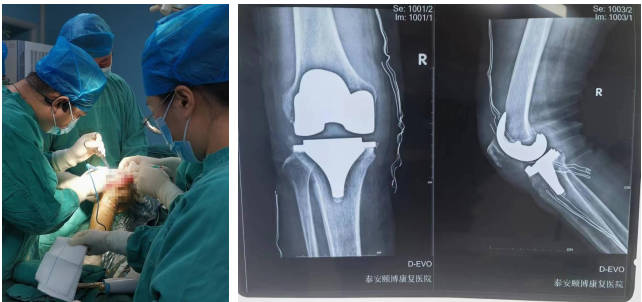

骨科

擅長腰腿疼痛的診治及四肢骨折、外傷的救治。開展了全膝、髖關(guān)節(jié)置換術(shù)、肘內(nèi)翻、足外翻畸形矯形術(shù)、經(jīng)皮椎體成形術(shù)、復(fù)雜手足外傷皮瓣修復(fù)術(shù)、復(fù)雜關(guān)節(jié)內(nèi)骨折復(fù)位固定術(shù)、骨腫瘤切除植骨固定術(shù)、椎間孔鏡椎間盤髓核摘除術(shù)、椎管狹窄椎管減壓術(shù)。